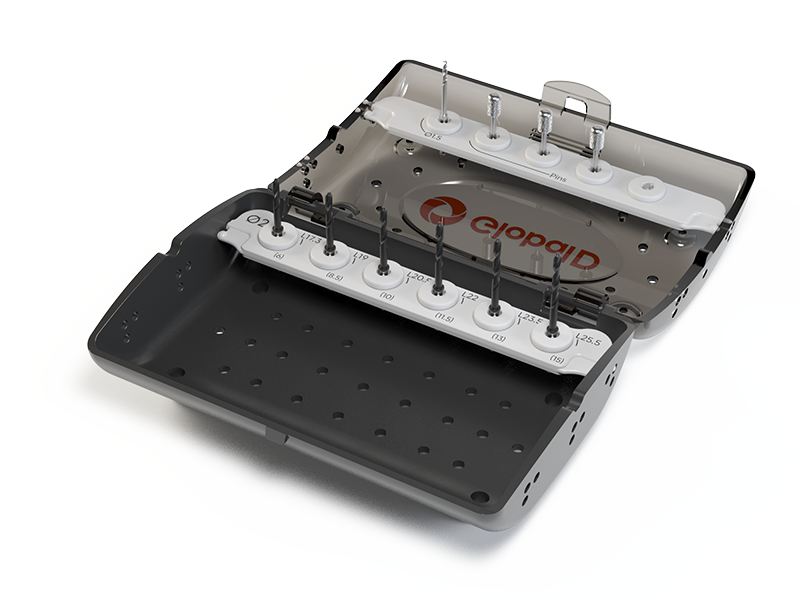

- Protocole ULTIMATE G42 & G52 : pas besoin de réducteurs intermédiaires, les forets assurent un guidage direct ultra-précis.

► Téléchargez la Plaquette Chirurgie Guidée ULTIMATE G42 & G52

► Téléchargez le Manuel de Chirurgie Guidée ULTIMATE G42 & G52